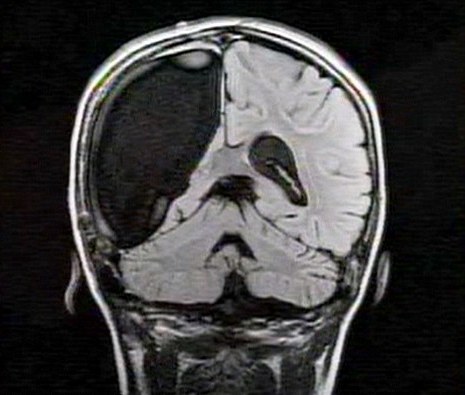

中新網(wǎng)3月26日電 據(jù)英國(guó)媒體26日?qǐng)?bào)道,一名9歲的英國(guó)女孩在經(jīng)歷了右腦切除手術(shù)后奇跡康復(fù),令醫(yī)生和家人無(wú)比震驚。

報(bào)道稱(chēng),現(xiàn)年9歲的卡梅倫•莫特在手術(shù)中切除了她整個(gè)右半邊的大腦,而在經(jīng)歷如此重大的手術(shù)后能迅速康復(fù),莫特的奇跡也讓醫(yī)生和她的家人驚嘆不已。年幼的莫特也沒(méi)有因?yàn)椴“Y而放棄對(duì)夢(mèng)想的追求。

卡梅倫莫特在3歲那年患上一種被稱(chēng)作大腦功能紊亂“拉斯穆森”綜合癥,這種病癥誘發(fā)患者的無(wú)序暴力行為和嚴(yán)重的癲癇。醫(yī)生建議,治療這種病癥只能通過(guò)嘗試消除引發(fā)此癥狀的大腦組織。而手術(shù)讓莫特失去了幾乎整個(gè)半邊的大腦。

據(jù)悉,莫特在手術(shù)后已經(jīng)可以跑動(dòng)和玩耍,她在術(shù)后的第四周離開(kāi)了醫(yī)院。醫(yī)生表示,雖然右半邊大腦的切除可能會(huì)給莫特帶來(lái)半身不遂的風(fēng)險(xiǎn),但孩子剩余的大腦仍具有很強(qiáng)的重組和布線(xiàn)能力。